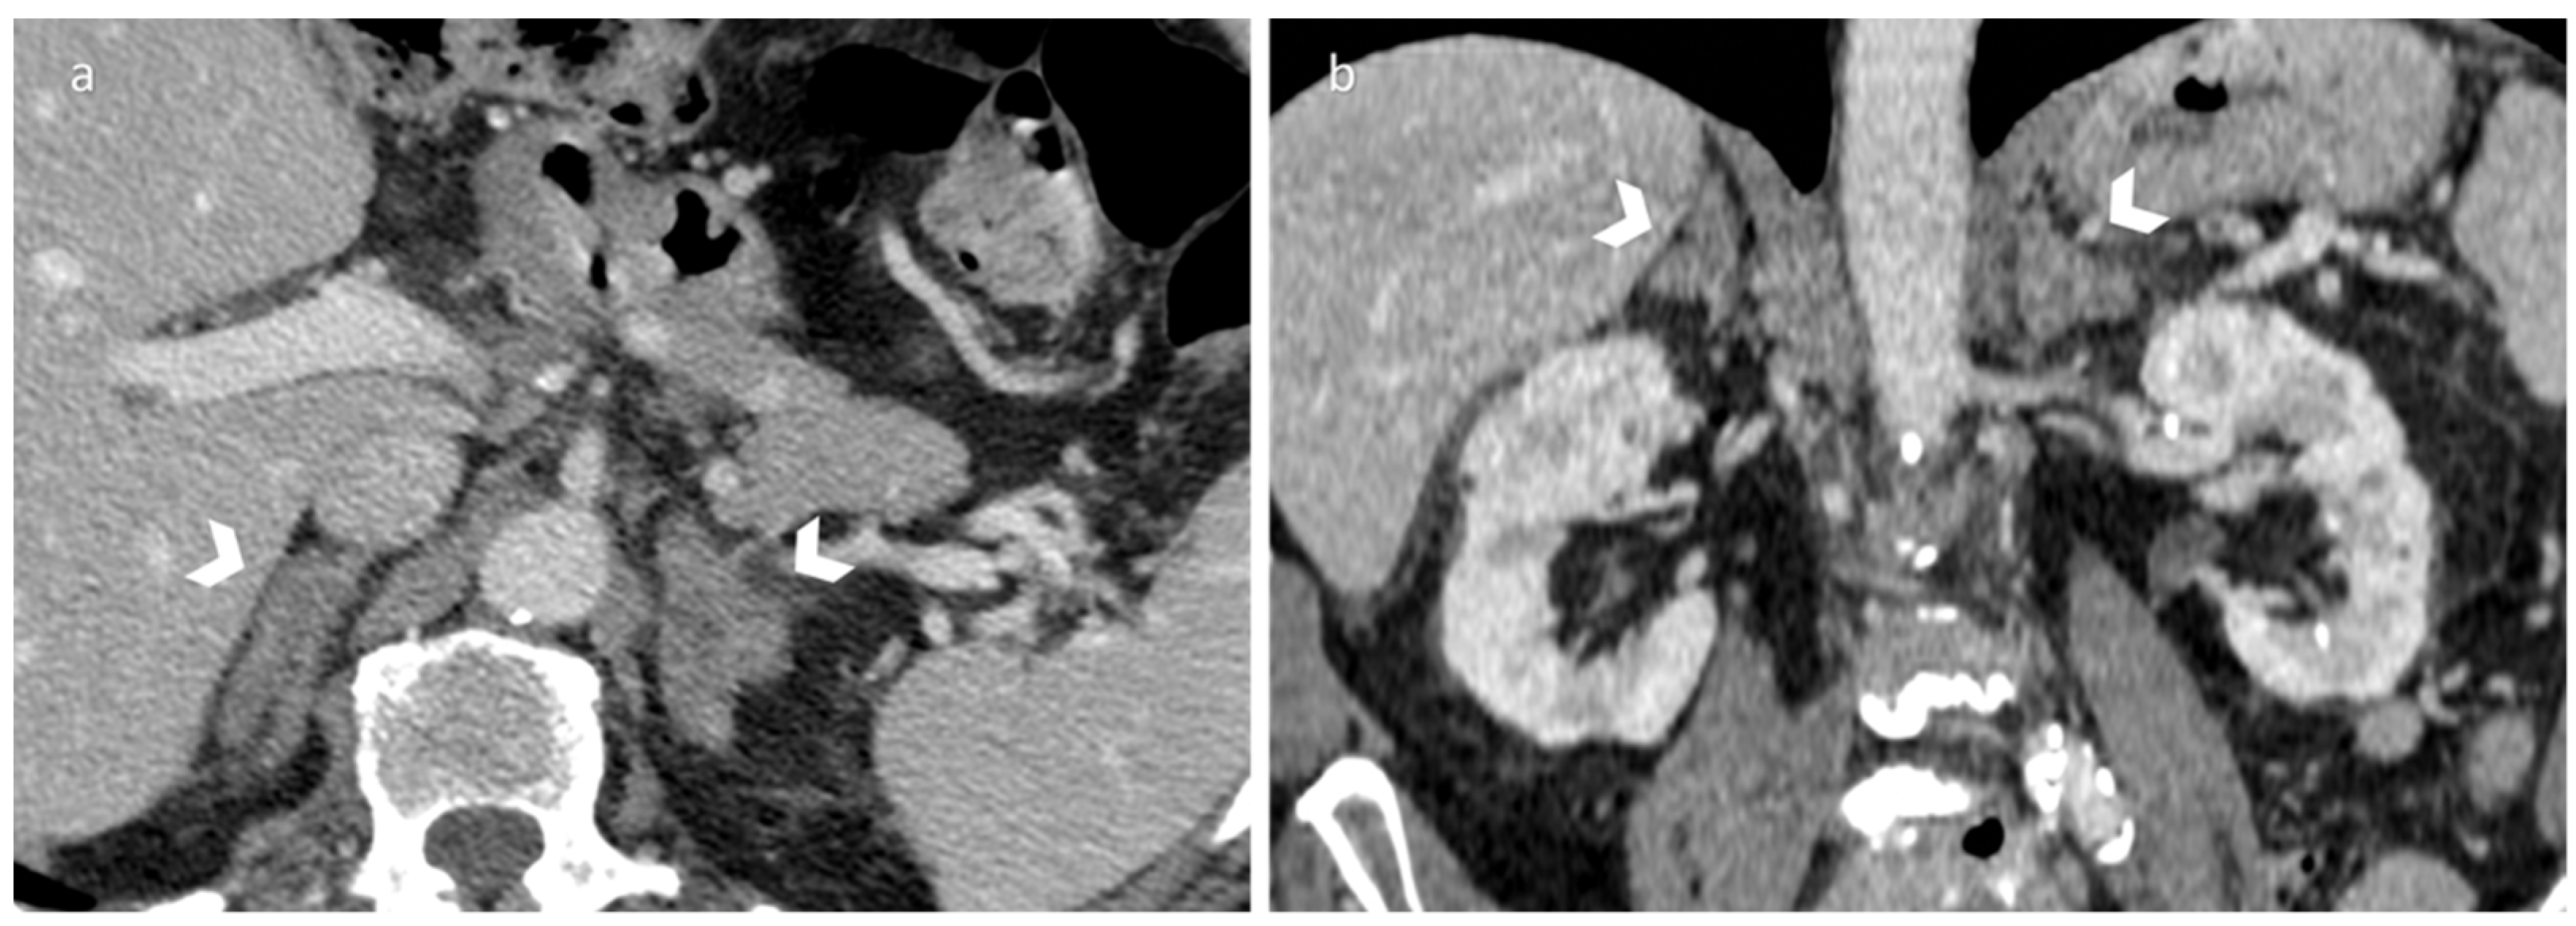

3.1. Pheochromocytoma